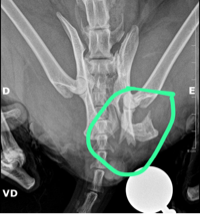

Pessoal, minha gatinha lola de 15 anos sofreu acodente no sabado (9/11), ela esta internada desde sabado. Ela precisa fazer duas cirurgias: uma pra colocar a bexiga no lugar e pra corrigir a fratura da bacia.